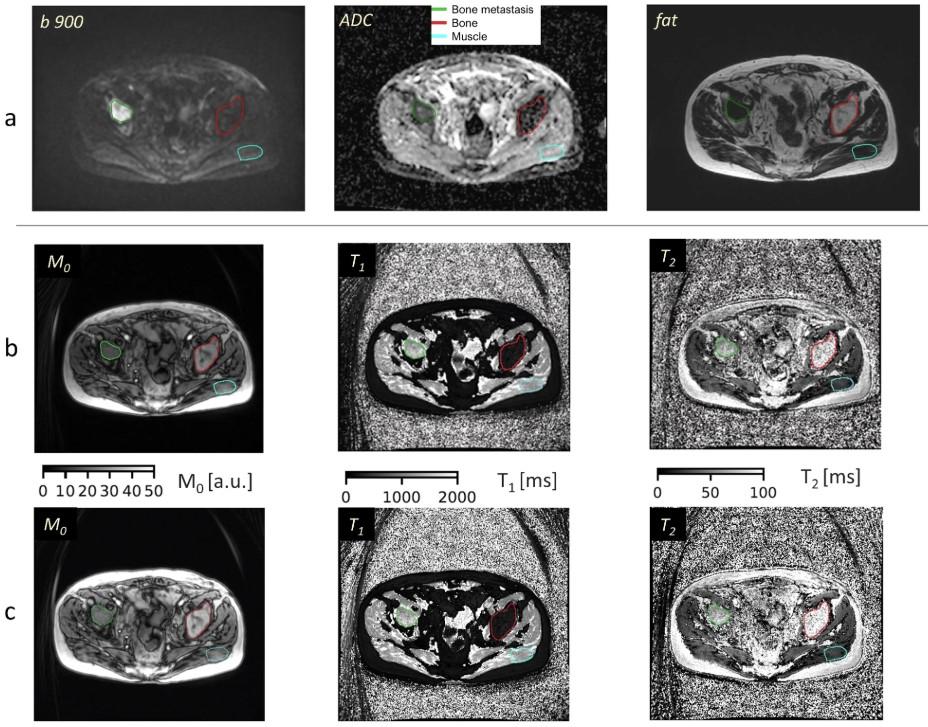

Mihaela Rata et al. explore the potential of MR fingerprinting (MRF) in quantifying treatment response by evaluating the repeatability of MRF-derived T1 and T2 relaxation times in bone metastasis, bone, and muscle in 20 metastatic patients. MRF allowed repeatable T1 and T2 measurements, which may help quantify treatment response.

πŸ”— buff.ly/3V4kOZz